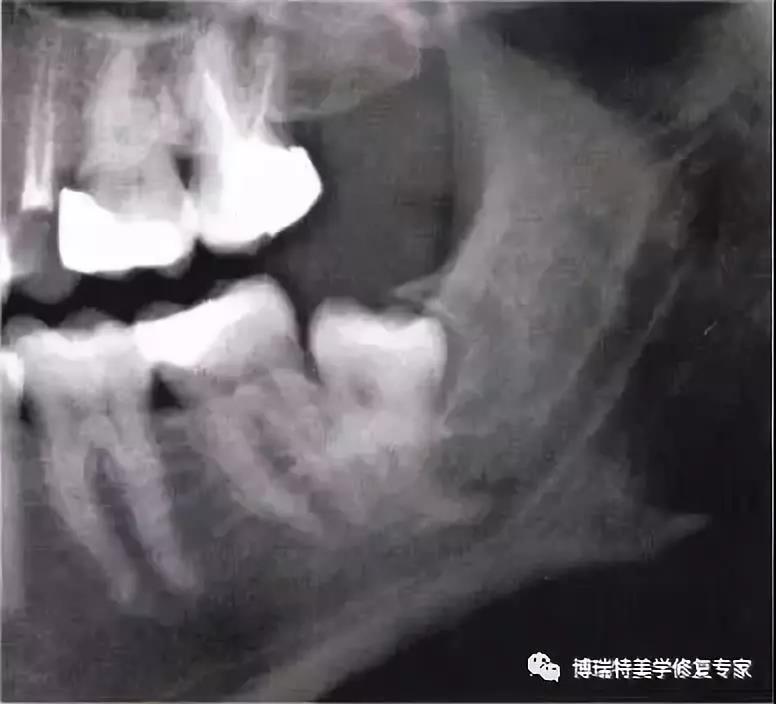

全颌曲面断层×线片,切割牙冠时应经过阻生牙远中面的牙颈部的釉牙骨质交界处。

下颌升支前缘的骨吸收区有利于牙片的取出。